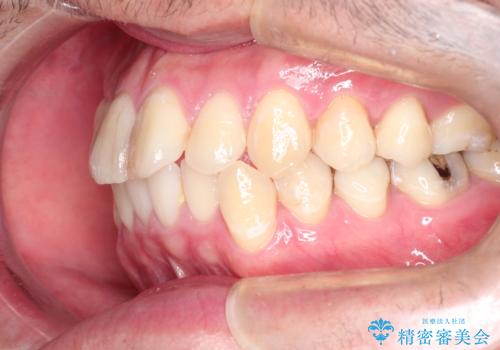

全体的ながたつきをインビザラインで改善

- 全体的ながたつきを主訴に来院されました。

歯と歯の間をわずかに削って、スペースをつくり並べる計画としました。

しっかりと、マウスピースの装着時間を守っていただいたので、スムーズに治療をおえることができました。